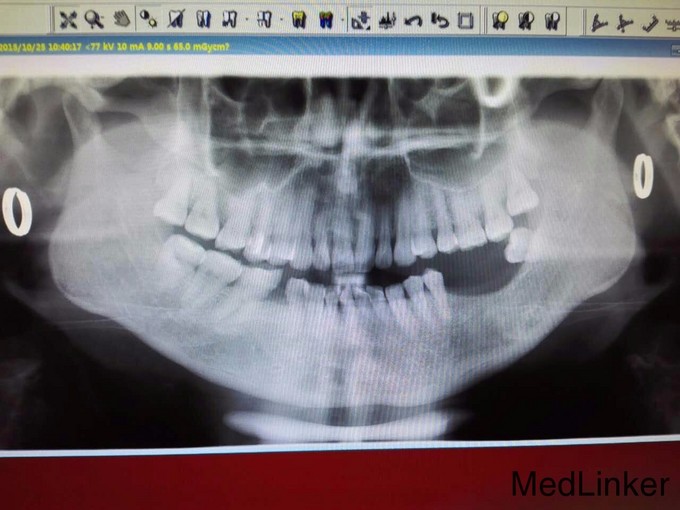

患者女48岁后牙缺失 欲种植

后牙缺失 欲种植